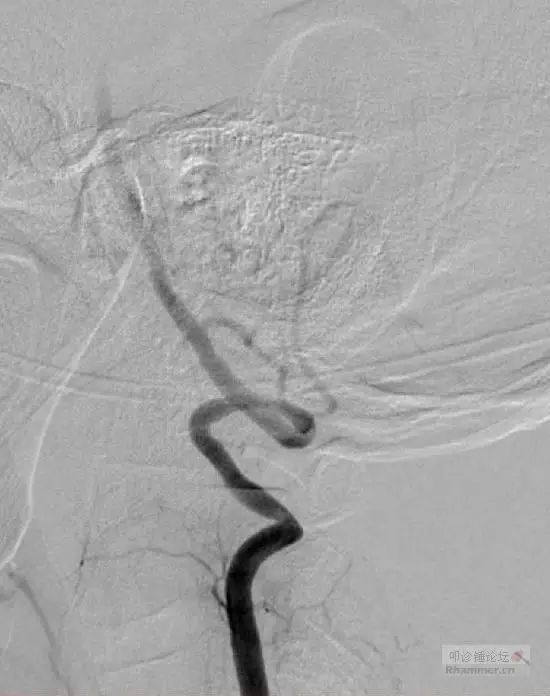

手术前动态右侧椎动脉DSA,(A)头正中位,血流正常(牙齿伪影),(B)头向左侧转动,C6水平右侧VA完全闭塞